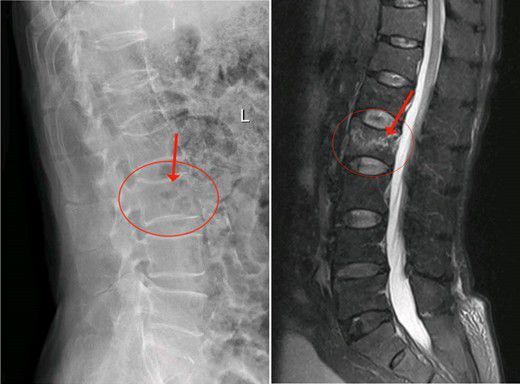

2月3日陳大伯由家人送到我院治療,收入外四科(骨科)。經腰椎MR檢查,發現腰椎第二椎體(L2)壓縮性骨折,椎體中間前緣壓縮變空。高齡患者如果采用保守治療,往往骨折遷延難愈,需要卧床至少1個月以上。老年人基礎疾病多,如陳大伯就患有高血壓、糖尿病、陳舊性心肌梗死等疾病,長期卧床容易誘發各類并發症而危急生命。而傳統開放性手術創傷大,高齡患者難以承受。這也是以往老年人最怕骨折的原因。

2月3日陳大伯由家人送到我院治療,收入外四科(骨科)。經腰椎MR檢查,發現腰椎第二椎體(L2)壓縮性骨折,椎體中間前緣壓縮變空。高齡患者如果采用保守治療,往往骨折遷延難愈,需要卧床至少1個月以上。老年人基礎疾病多,如陳大伯就患有高血壓、糖尿病、陳舊性心肌梗死等疾病,長期卧床容易誘發各類并發症而危急生命。而傳統開放性手術創傷大,高齡患者難以承受。這也是以往老年人最怕骨折的原因。

△腰椎第二椎體(L2)壓縮性骨折